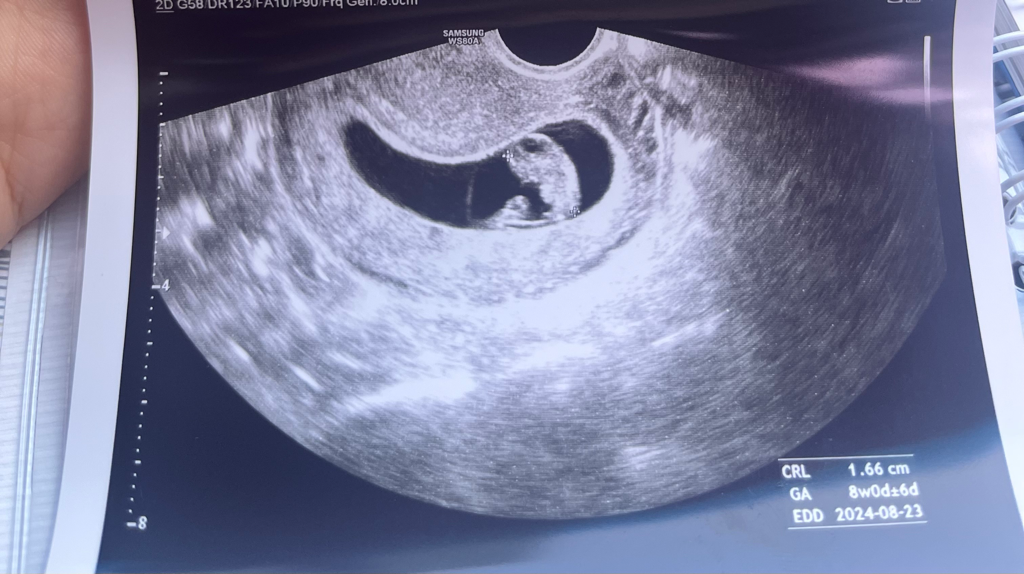

임신8주 초음파 보고왔는 데 사진상 어떤 부분이 난황인가요?

임신8주 초음파

오늘 산부인과가서 초음파보고 설명듣고 왔는 데 팔다리 생긴 것에 신기해서 난황도 알려주셨는 데 잘 기억이 안나서요 ㅎㅎ

난황위치가 현재 아기집 왼쪽에 있는 ㄱㅔ 맞나요 ?